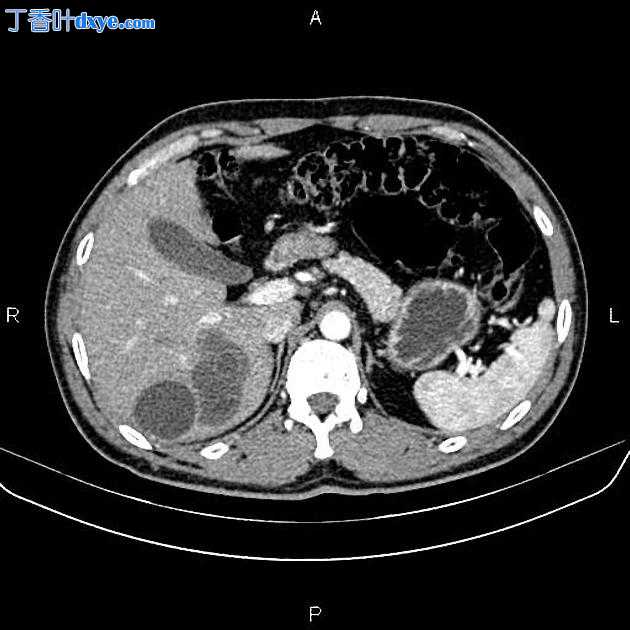

3.jpeg

Axial C+ portal venous phase

在右肝叶小于 55 mm 处可见三个相邻的厚壁囊性病变。

此外,还描绘了一个直径为 15 毫米的低密度肝病灶,位于第 4 肝段(Couinaud 的命名法),显示早期外周、结节状强化和向心性充盈。特征与血管瘤最相容。